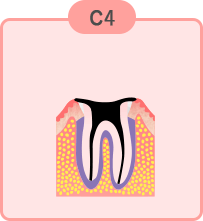

最重度のむし歯

歯全体がむし歯に侵され、根の先や根の周りにも影響がでています。